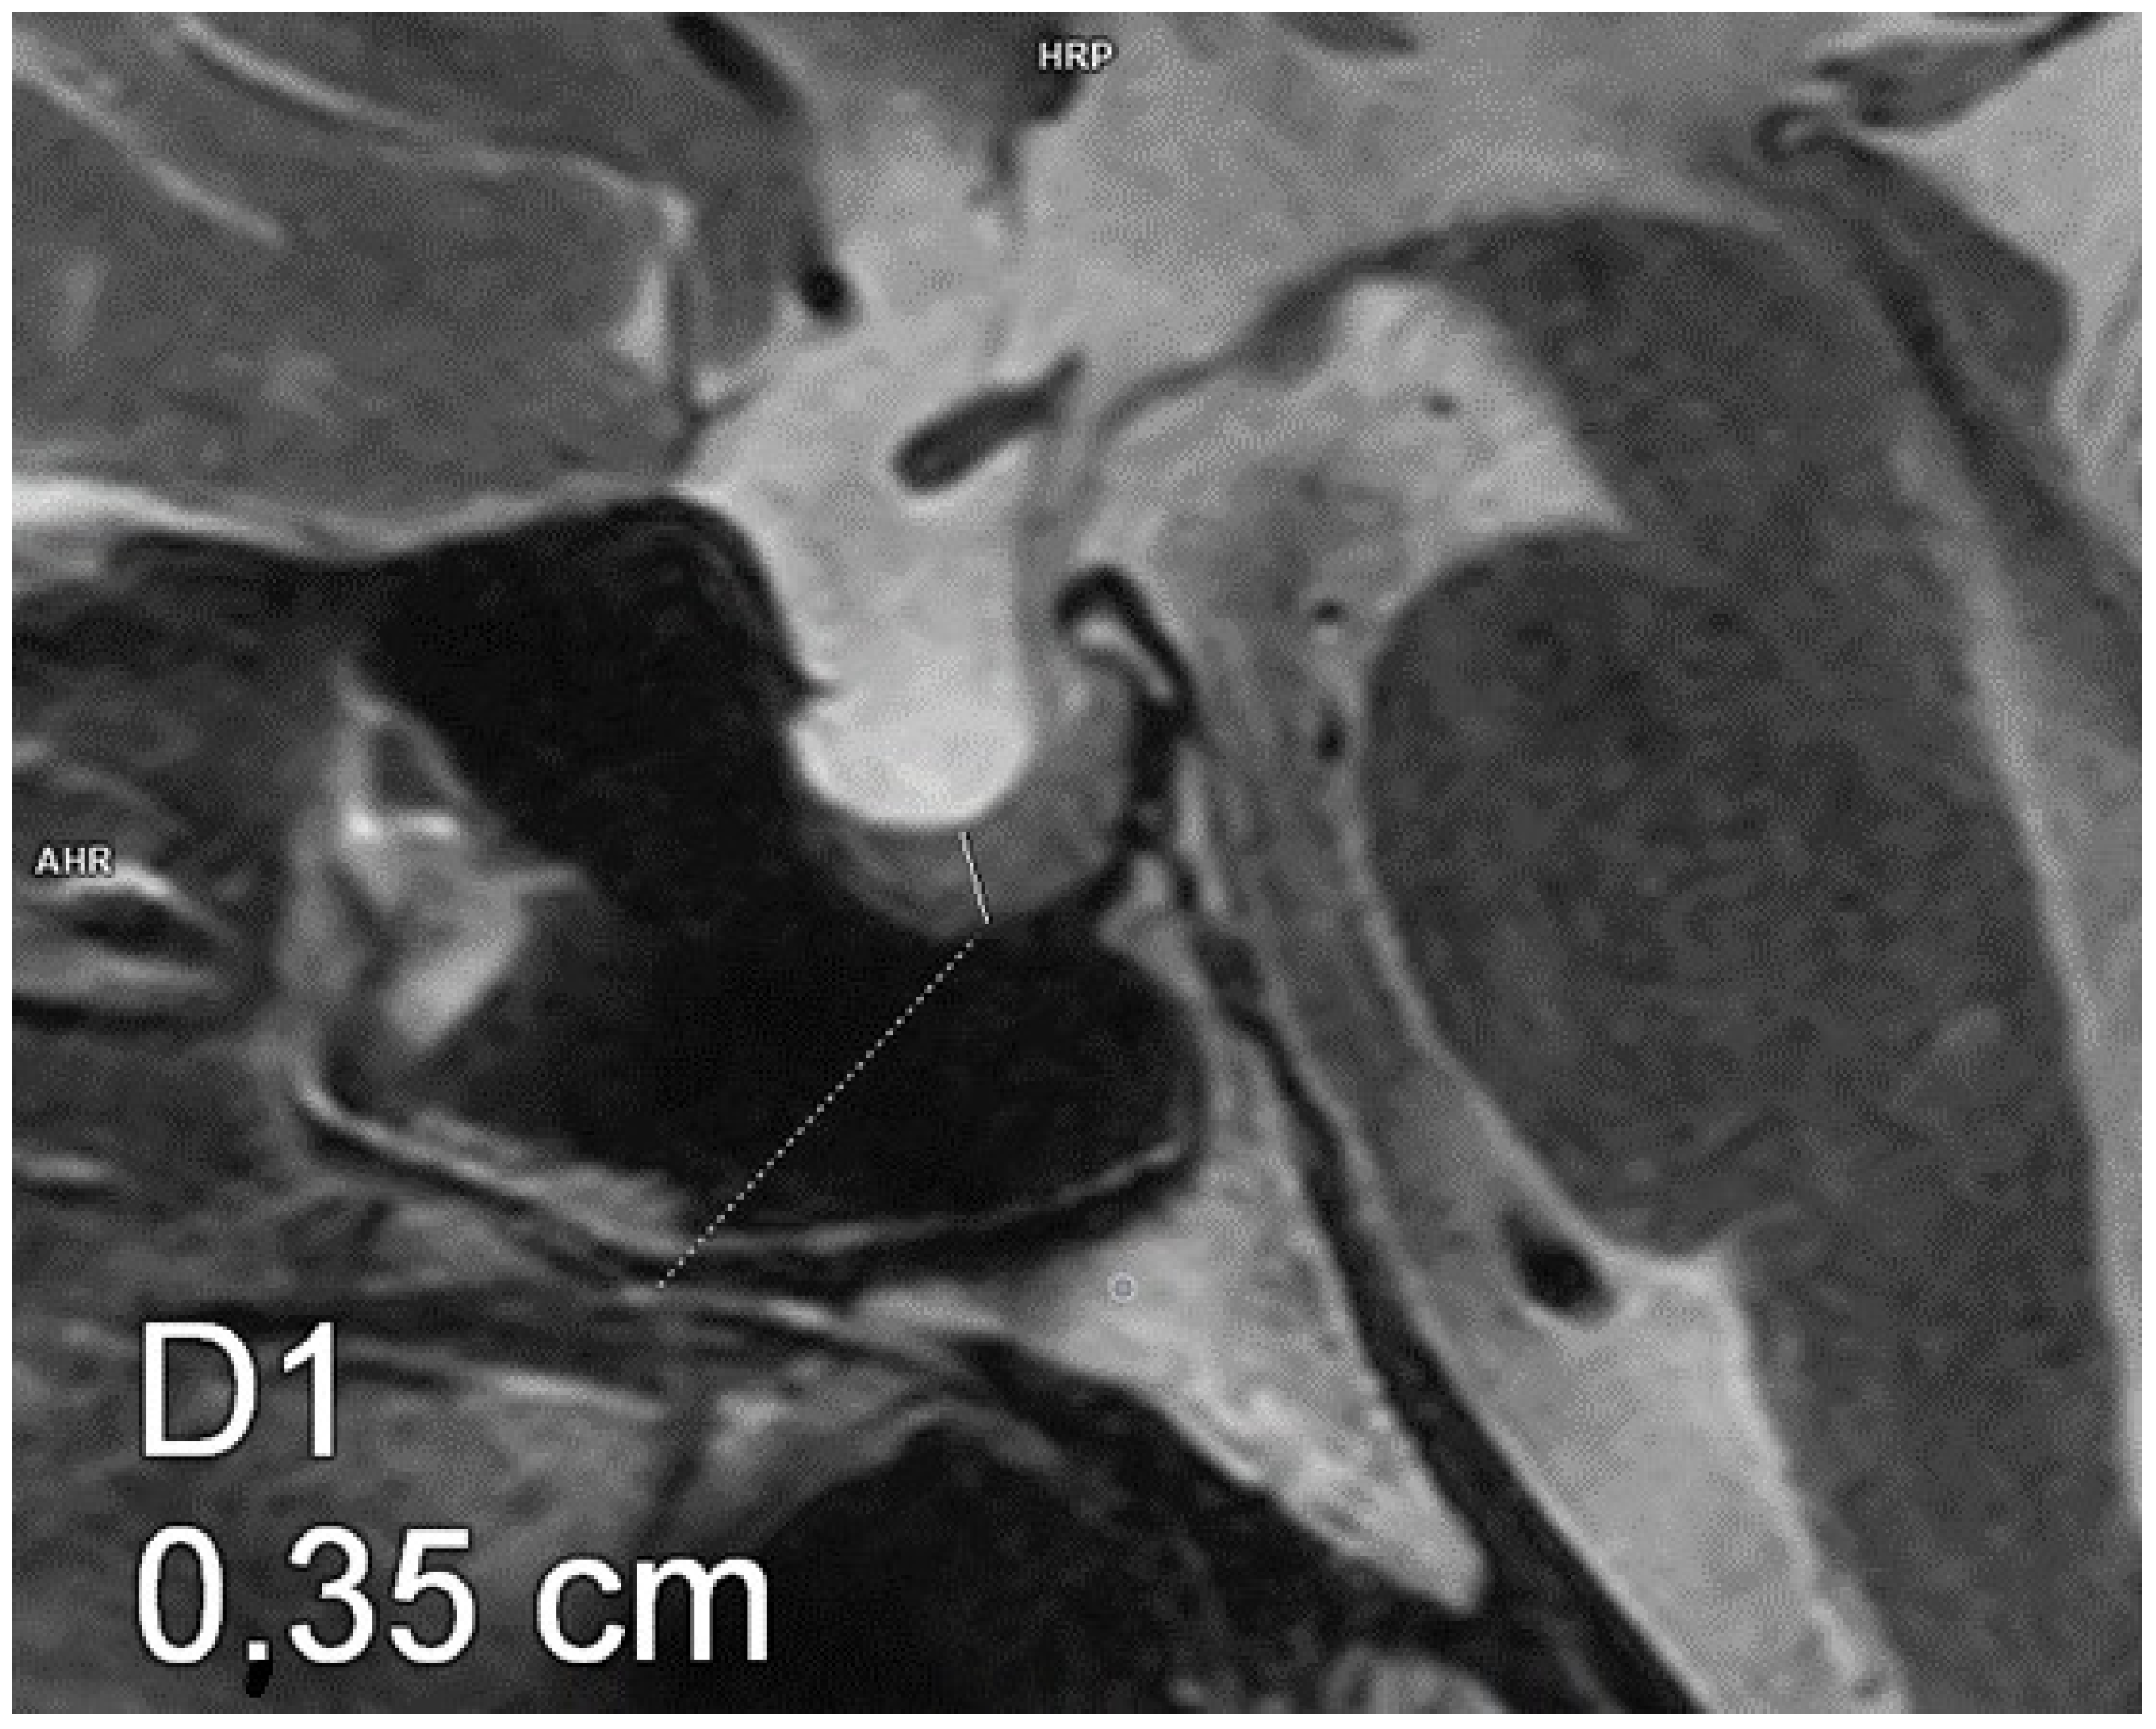

Figure 1.

Empty sella. Magnetic resonance imaging, T2-weighted image, sagittal plane. The craniocaudal diameter of the pituitary gland is 1.4 mm.